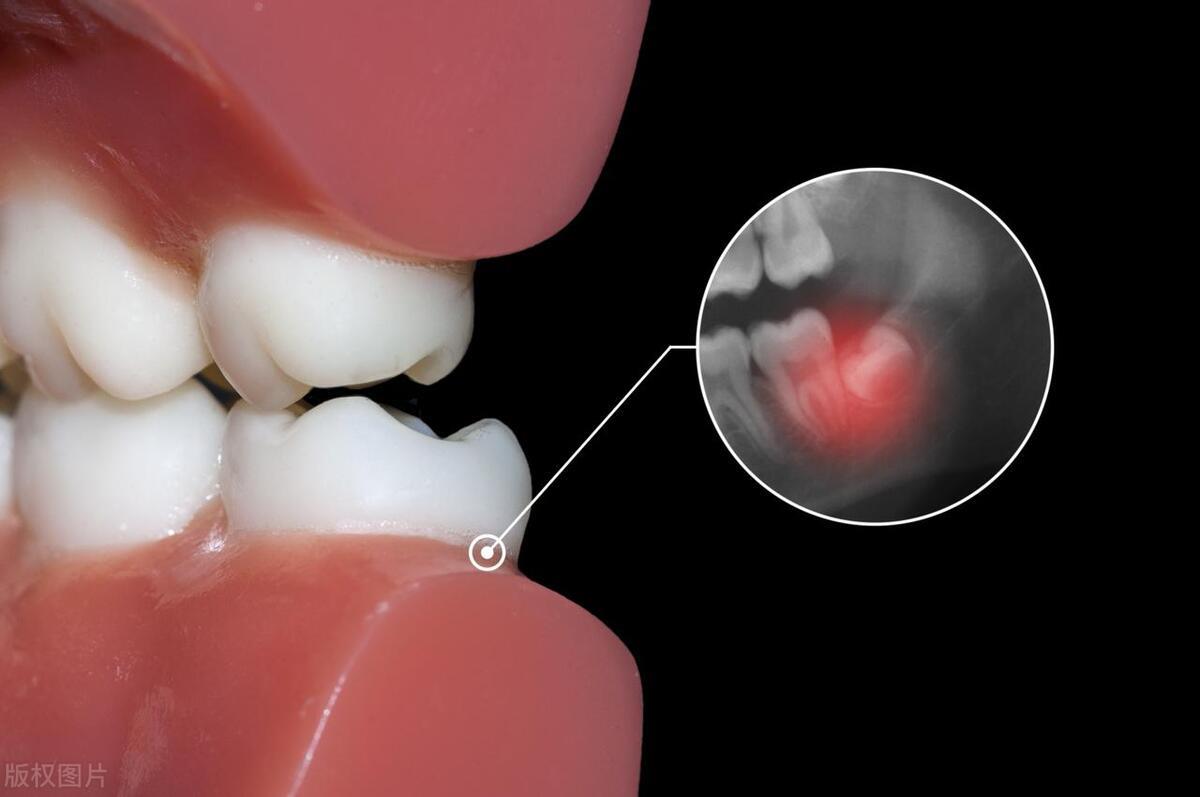

智齿:进化的遗留物

让我们从智齿说起。智齿,这个通常在人成年后(16-25岁)才萌出的牙齿,常常因为其生长位置不佳而引发各种问题。在现代社会,由于人类食物结构的改变和颌骨大小的缩小,智齿的生长空间变得极为有限,这导致它们往往无法正常萌出,甚至引发疼痛、感染等问题。据统计,约有30%的成年人会选择拔除智齿,以避免其带来的不适和潜在的健康风险。

史前岁月,智齿或成关键,赋予人类更强咬合力,征服硬质食物难关。然而现今,智齿往往转变为口腔健康的“潜在威胁”。因此,对于经常发炎、影响其他牙齿生长的智齿,及时拔除不仅不会对身体造成损害,反而有助于维护口腔健康,降低牙周炎等口腔疾病的发病率。